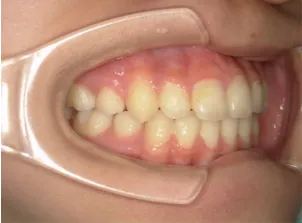

治療後⑩高2:17y7m 抜歯治療終了

口元の治療前後:15y5m→17y7m スッキリしました